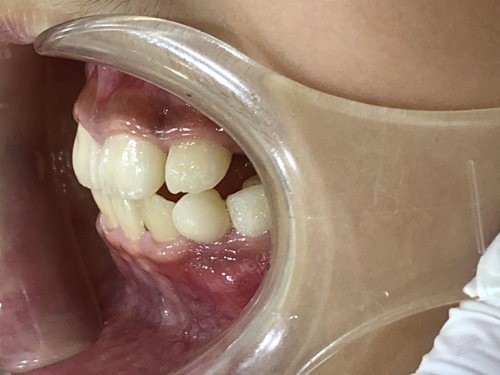

• BEFORE

症例集 インビザライン 右横

スペース不足を整えるために、歯の表面にアタッチメント(白い突起)をつけ、IPR(歯と歯の間を削る)を行いました。

スペース不足を放置していた場合、叢生と言って歯が重なって生えてくる可能性の高い状態でした。

そのため、治療開始時には右下の前から3番目の永久歯の生えるスペースがありませんでした。

矯正治療を行うことで、スペースができ、治療後には正しい位置に生えています。